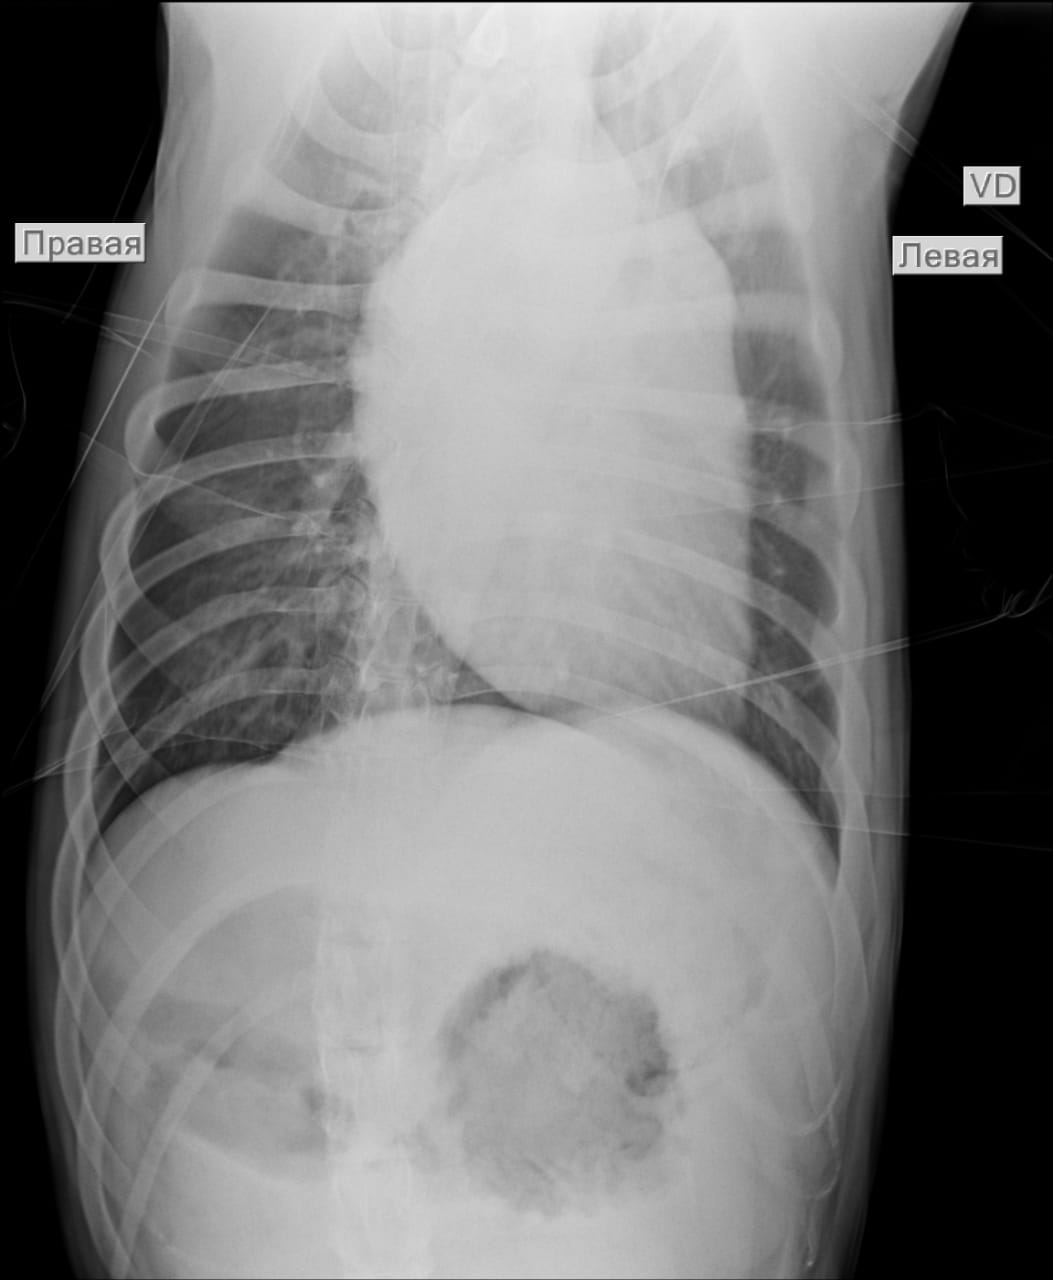

Анализы Арчи. Сердца и легких

Сегодня Арчуна Ирина возила на рентген легких и сдали анализ мочи. Результат анализа мочи готов будет завтра. Рентген легких выставляю.

Ирина, ждем твоего вердикта по рентгена и можно ли нам готовить Арчи к операции по глазам.

Лучше чем было, но явно не норма:(